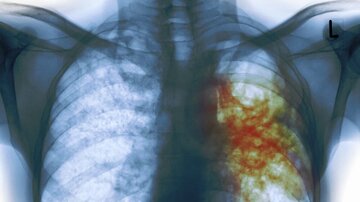

سِل یک بیماری عفونی و در بسیاری موارد مرگبار است که توسط نوعی باکتری به نام مایکوباکتریوم توبرکلوزیس ایجاد می شود و بیشتر ریه ها را درگیر می کند هرچند که می تواند سایر قسمت های بدن را نیز درگیر کند.